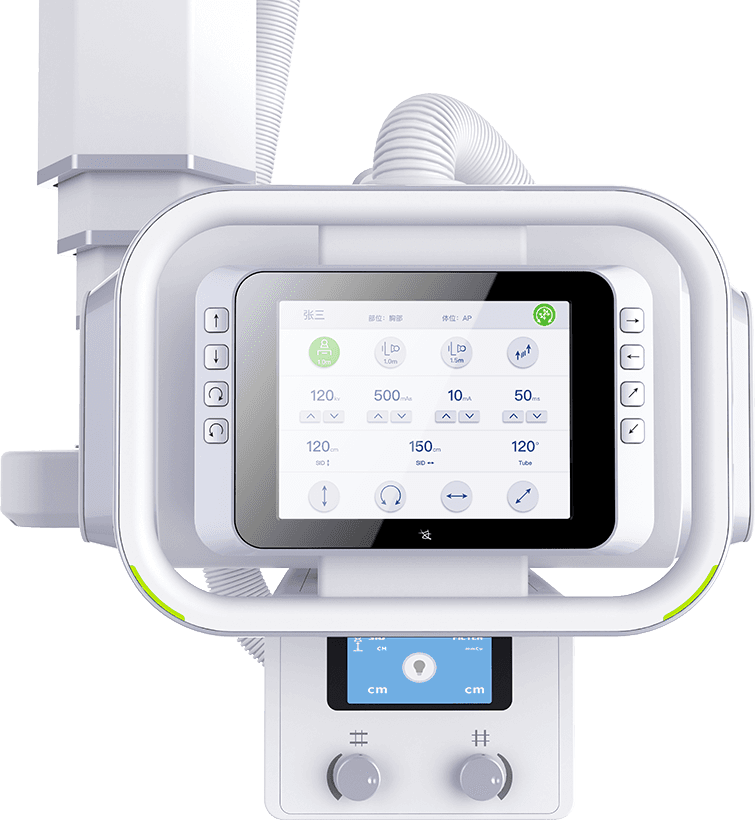

ЦЗДЬґҐїШґуЖБ

Тєѕ§ґҐГюЖБЈ¬ґҐГюІЩїШЙи±ёФЛ¶ЇЈ¬КµК±µчХыёчАајмІйІОКэЈ¬

ІўН¬ІЅПФКѕ»јХЯРЕПўЎўЖШ№вІОКэј°°ЪО»МбКѕЎЈ -